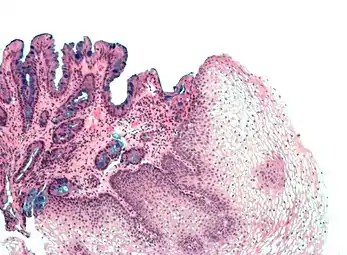

H&E stain of biopsy of normal esophagus showing the stratified squamous cell epithelium.

A stratified squamous epithelium consists of squamous (flattened) epithelial cells arranged in layers upon a basal membrane. Only one layer is in contact with the basement membrane; the other layers adhere to one another to maintain structural integrity. Although this epithelium is referred to as squamous, many cells within the layers may not be flattened; this is due to the convention of naming epithelia according to the cell type at the surface. In the deeper layers, the cells may be columnar or cuboidal.[1] There are no intercellular spaces. This type of epithelium is well suited to areas in the body subject to constant abrasion, as the thickest layers can be sequentially sloughed off and replaced before the basement membrane is exposed. It forms the outermost layer of the skin and the inner lining of the mouth, esophagus and vagina.[2]